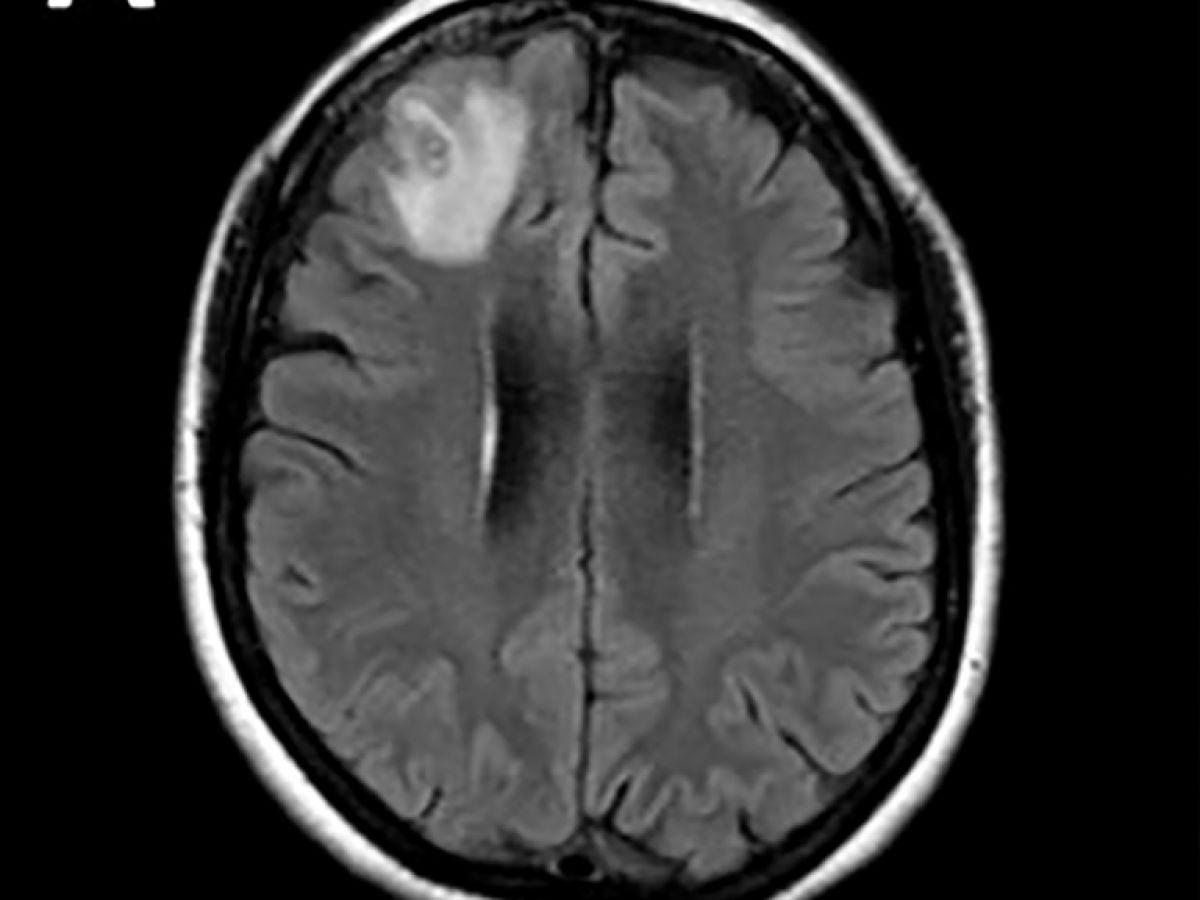

Africa-Press – Benin. Un ver rond, qui parasite généralement les serpents, a été découvert pour la première fois sur un être humain. Il a été extrait « vivant et se tortillant » du cerveau d’une Australienne lors d’une intervention chirurgicale, ont annoncé mardi des médecins australiens. Les médecins ont découvert une « lésion atypique », grâce à un examen IRM, dans la partie frontale du cerveau de cette femme âgée de 64 ans qui souffrait de pertes de mémoire.

« À notre connaissance, c’est également le premier cas impliquant le cerveau d’une espèce de mammifère, humaine ou autre », a-t-il précisé. Cette découverte a fait l’objet d’un article dans la revue « Emerging Infectious Diseases ». Les scientifiques pensent que l’Australienne a été parasitée par des plantes comestibles, probablement contaminées par des larves présentes dans des excréments de serpents. Le parasite, dont la « structure en forme de fil » est apparue sur les scanners cérébraux, a ensuite été identifié grâce à des tests ADN. « Il n’est jamais facile ni souhaitable d’être le premier à être malade de quoi que ce soit au monde », a ajouté le Dr Senanayake, « je ne saurais trop exprimer notre admiration pour cette femme, qui a fait preuve de patience et de courage tout au long de ce processus. » Selon le Dr Senanayake, il est « probable que d’autres cas soient identifiés à l’avenir ».